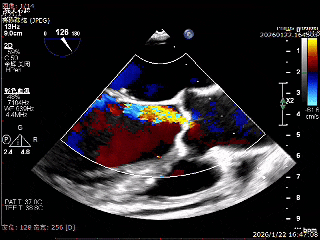

术前超声影像

左室长轴超声可见大量反流

可见二尖瓣明显反流

术后超声影像

左室长轴超声无明显反流

二尖瓣反流可见改善